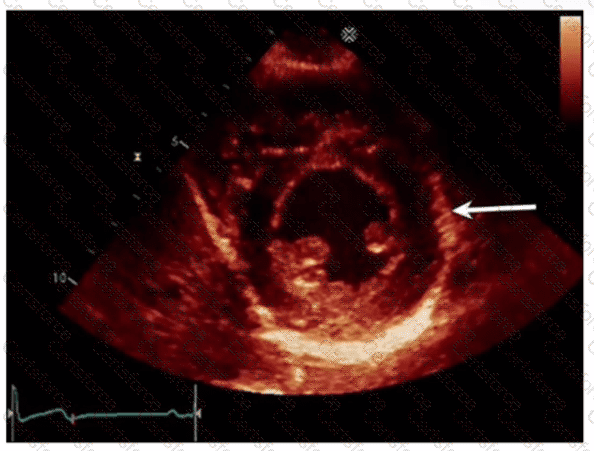

Which left ventricular regional wall segment is indicated by the arrow on this image?